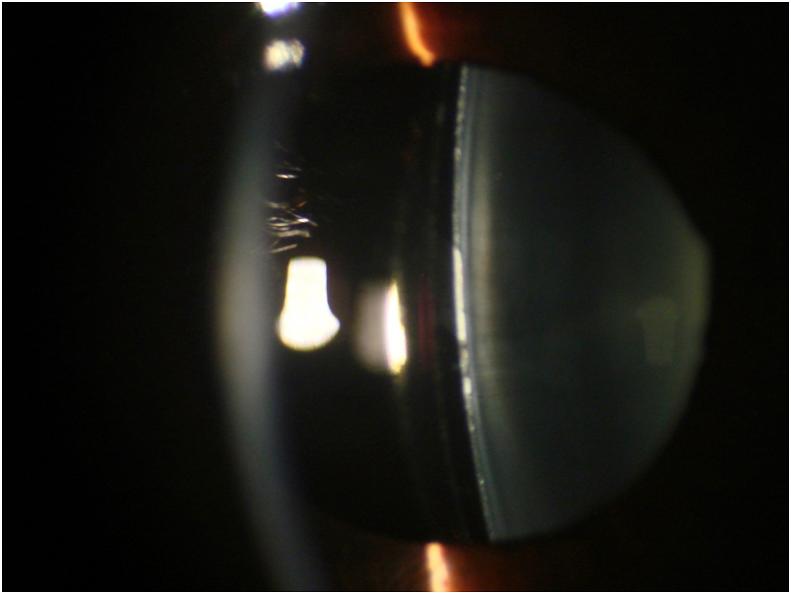

Transient crystalline lens deposits following the insertion of a phakic sulcus-fixated collamer intraocular lens in a hyperopic eye.

The purpose of this study was to report crystalline lens deposit formation following ICL implantation for the correction of hyperopia.

A 23-year-old male presented at the American University of Beirut Medical Center in 2008 seeking refractive surgery for hyperopia. His cycloplegic refraction was +7-1.25 × 115° and +7-1.00 × 115° in the right and left eyes, respectively, yielding a vision of 20/20 bilaterally. The patient underwent right eye insertion of a non-toric phakic sulcus-fixated collamer lens 2 weeks after undergoing peripheral iridotomies. The early postoperative course was complicated by anterior chamber inflammation and the appearance of diffuse whitish precipitates on the anterior surface of the crystalline lens, hypotony, and a mid-dilated mildly reactive pupil. With the prompt administration of topical and systemic steroids, the anterior chamber reaction subsided, and the anterior capsular deposits gradually resolved peripherally with some remaining centrally over the course of several weeks. The patient's visual acuity at 6 months was 20/20.

Adequate viscoelastic removal and minimal iris stimulation seem to be essential to avoid this condition in hyperopic implants that lack a central port. Additionally, prompt treatment can minimize visual impairment and hasten visual recovery.